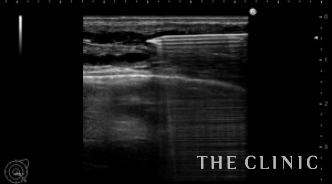

ヒアルロン酸は通常は乳腺と大胸筋の間に注入しますが、時々大胸筋内に注入されて炎症を起こしたり、しこりになる場合があります。

今回紹介する方も以前炎症をおこしたためヒアルロン酸を溶解しました。